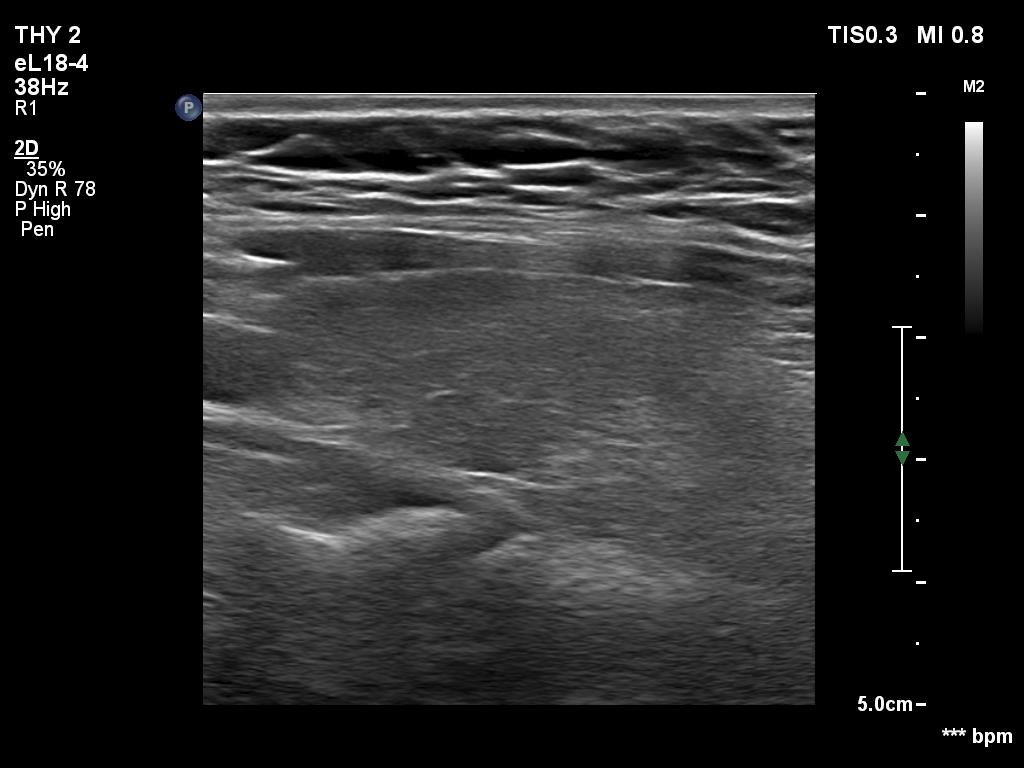

Ultrasonography. The thyroid was echonormal. Using higher frequency three discrete hypoechoic lesions were found, one in the middle dorsal part of the right lobe, one in the middle and a third one in the lower dorsal part of the left lobe. By decreasing the frequency, the presence of only the third one could be confirmed.

Comment. It is a rule that larger the distance from the probe worse the permeability of ultrasound wave. This can lead in certain patients (overweighted ones or frequently in men) that the dorsal part of the thyroid lobe can deceptively look darker, i.e. hypoechoic. If we have any doubt, by lowering the frequency i.e. increasing the penetrance, the real situation can be much better to judge.

This happened in this patient. If we would trust the pattern gained by higher frequency settings, we would falsely diagnose at least one additional nodule.